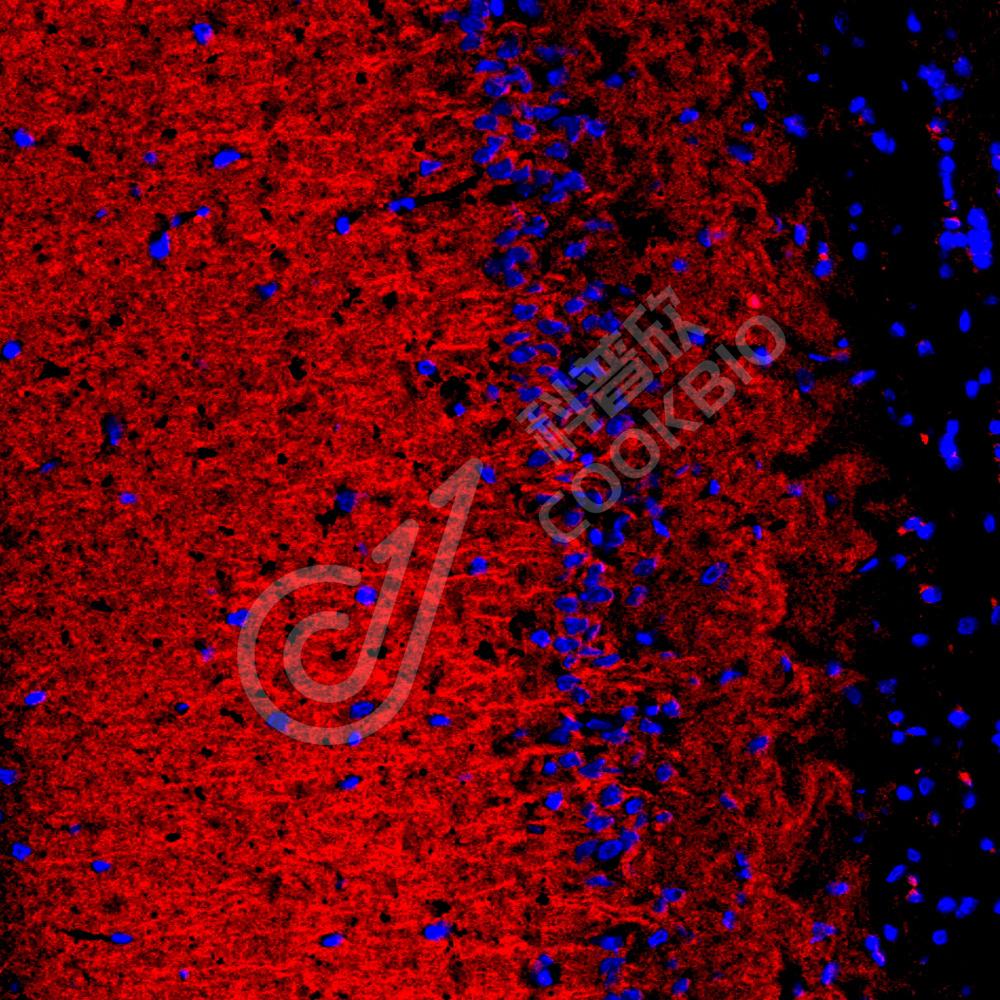

IF检测Tau蛋白(货号 K1334827)(红色).

样品: 小鼠脑, 4%多聚甲醛 (货号KSG1101) 固定12-24小时.

抗原修复: Tris-EDTA抗原修复液(pH 9.0) (KSG1203), 98℃, 20分钟.

封闭: 3% BSA(货号KSGC305010)的PBS溶液, 室温孵育30分钟.

—抗: 1: 1500稀释, 4℃ 孵育过夜.

二抗: Cy3标记山羊抗兔IgG (H+L) (货号KB63909), 1: 300稀释, 室温孵育1小时.